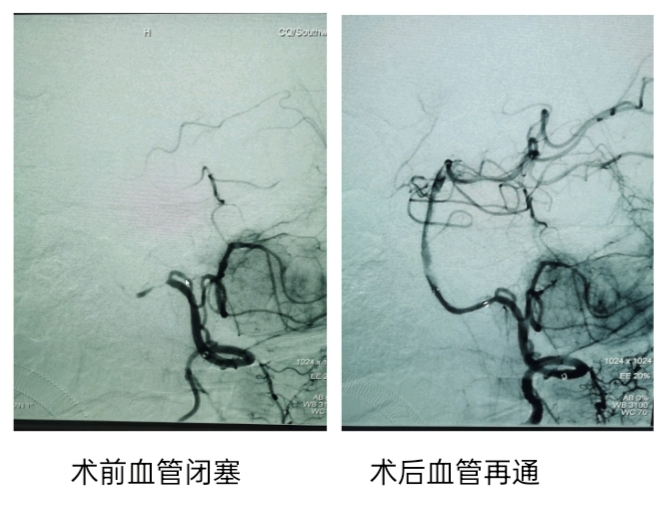

紧接着,杨婆婆被送往介入手术室,立即启动急诊取栓手术。手术过程中,神经内科副主任医师刘渠先是利用脑血管造影确定杨婆婆的血栓位置,再利用动脉取栓装置,从她脑中取出了血栓。手术最终顺利结束,过程持续约半个小时。

术后第二天,杨婆婆瘫痪的肢体就能抬离床面了。目前,杨婆婆的恢复情况良好,有望于近期出院。